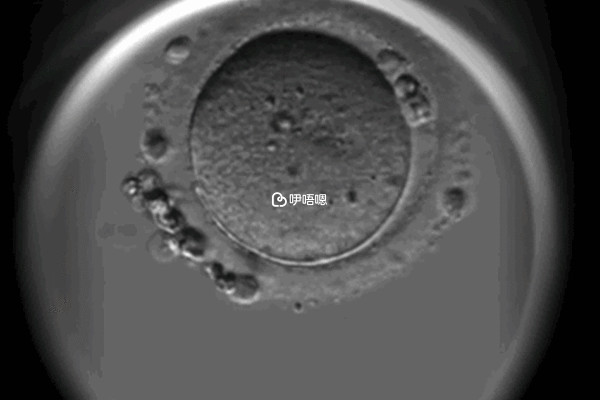

同性試管是需要到精子庫醫院先選擇好精子的,然後再選擇a卵b懷的方式,用一個女性的卵子和男性的精子培育出胚胎,之後再移植進另一個女性的體內。這樣能讓兩人在懷孕的過程中都有參與感,之後只需要按時進行產檢即可。